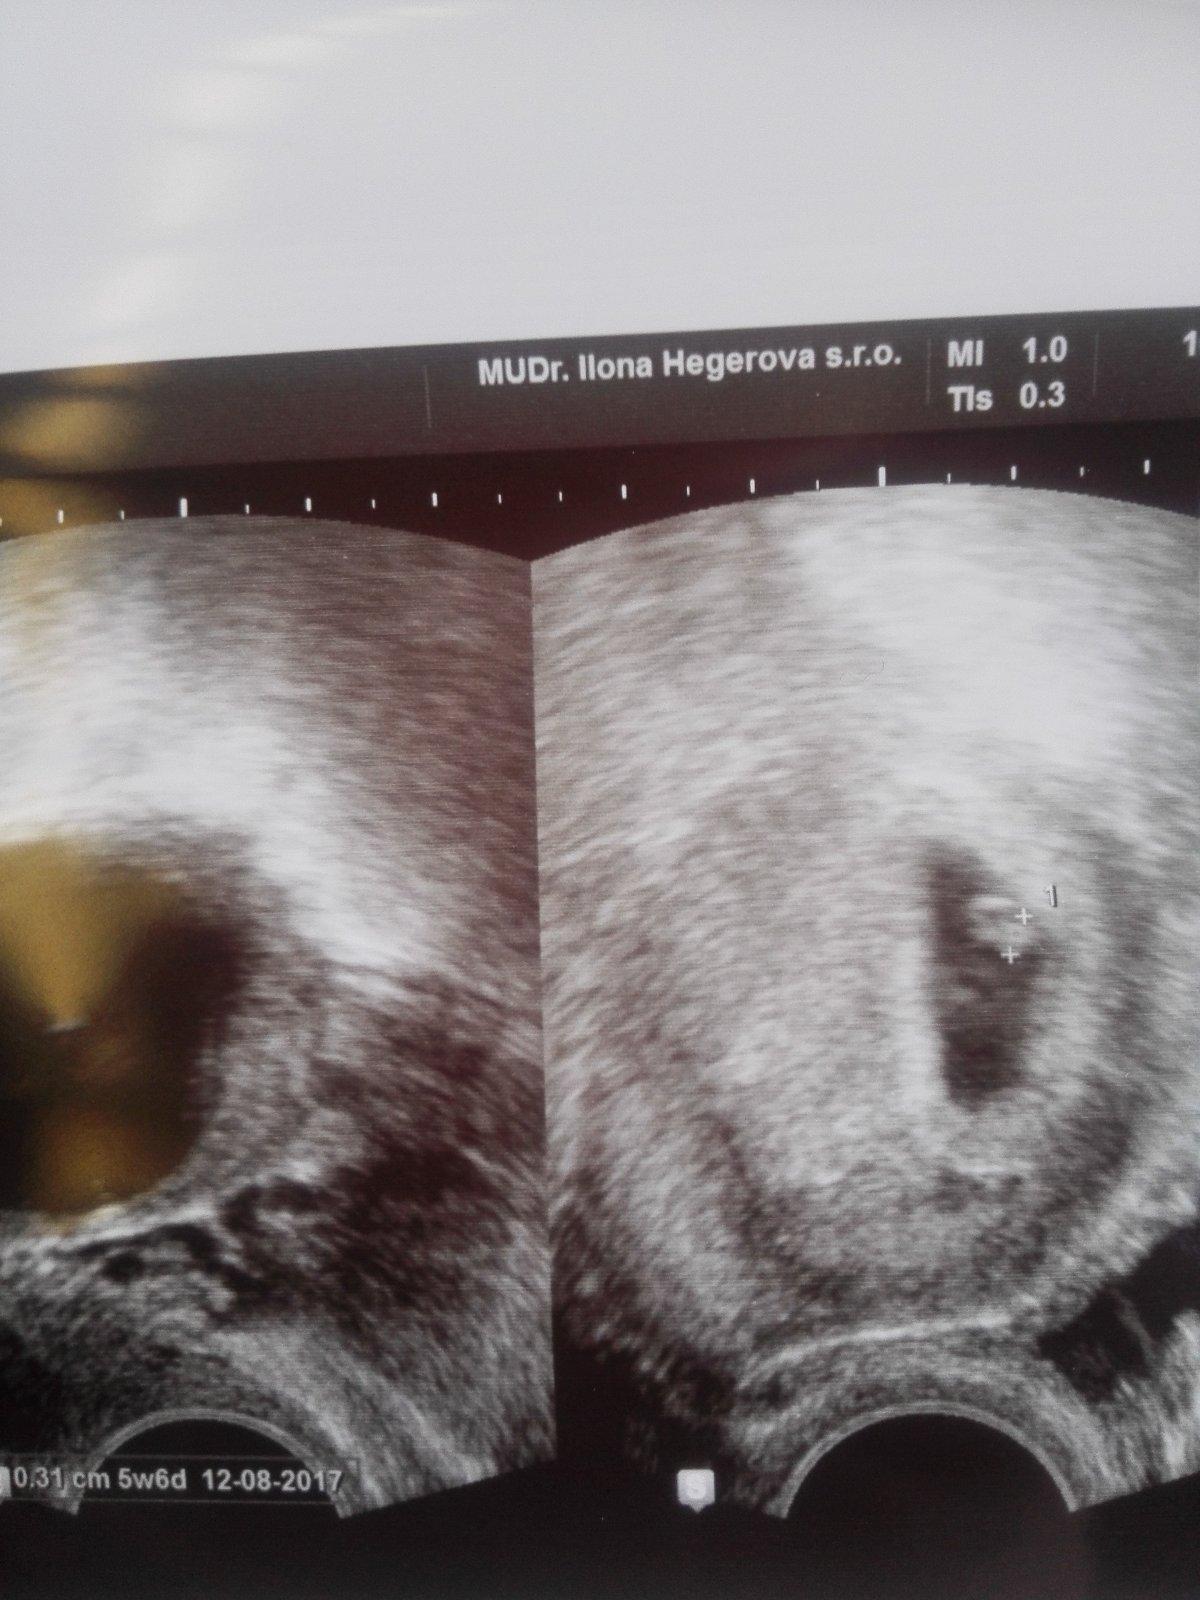

Holkyyy,mame kontrolu u pani doktorky za sebou a dopadlo to výborně! 🙂 tak bud je prdousek rekordman v rustu nebo nevim,ale v po na pohotovosti mi rekli,ze jsem 4+3 a o ctyri dny pozdeji mi moje dr rekla,ze jsem 5+6 🙂 takze jen o dva dny pozadu ale uz nam bilo krasne srdicko😍 jsem tak stastna a doufam,ze uz bude jen dobre a miminkovi se u me bude darit jak v pokojicku :-* pry se to pani dr tentokrat libi,ze to nechce zakriknout,ale ze je to ok 🙂 uz se mam pry objednat na screening mezi 25.1.-5.2.